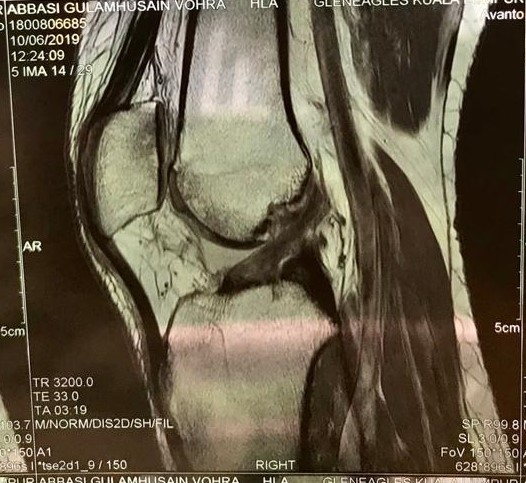

左が受傷直後、右が受傷6ケ月のMRI

治療開始が受傷後1ヶ月という急性期が過ぎつつあるということと、前十字靭帯の断裂の仕方が今までに見たことのない複雑さを呈していたことから、解剖学的自然治癒は困難であると予想していた。私の予想に反して、6ヶ月目のMRIにおいて、はっきりと靭帯の連続性が確認されたことは驚きであった。機能的には、患側に筋力低下が見られるものの、日常生活においては問題ないレベルまで回復している。患側の筋力が戻るまでリハビリは継続していく予定である。

He ruptured his right ACL completely in December,2018. He started the Naturalization Therapy from the one month after the injury. We had the internet sessions through the Skype once in every 2 weeks for the first 3 months and once in 1 month from the 4 months. At first, there were the difficulties for the anatomical healing, because it was the severe and complete ACL tear which had torn in the unusual way. Moreover, it was late that he started my therapy because the acute period was almost passing. Contrary to my expectations, the MRI shows that his completely torn ACL has healed clearly and anatomically. The Naturalization Therapy enables the ACL tear to heal naturally without any complication. As long as the blood supply and the anatomic reduction are secured, the natural healing process will work even on the ACL.